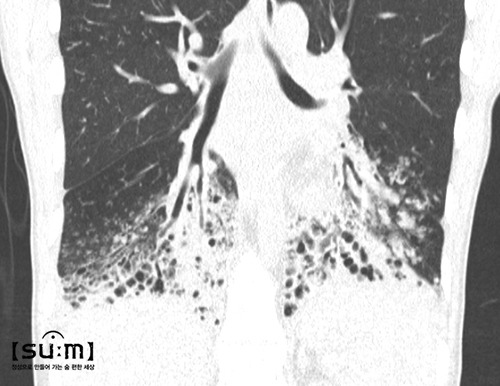

초록색 가래

초록색에 가까운 가래는 인플루엔자의 간균, 녹농균 등에 의한 세균에 감염이 됐을 때 나타난다. 노란 가래보다 더 심각한 감염 상태를 뜻한다. 만약 가래 색깔이 처음에는 벽돌색이었다가 점차 초록색으로 진하게 바뀐다면 '폐렴'의 주요 증상 중 하나인 청색증일 확률이 높다. 호흡곤란 때문에 혈액의 산소 운반 능력이 떨어지면 가래 색깔과 입술이 푸른색으로 변하기 때문이다.

333.jpg